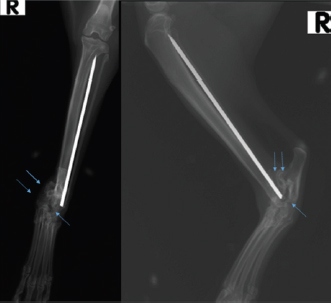

Case Details

Fig. 5. Radiographic follow-up examination 16 weeks after pantarsal arthrodesis revealing an almost complete fusion of the arthrodesis.